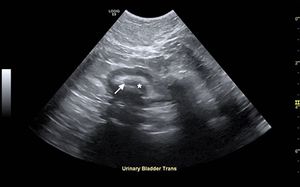

Examine the ultrasonograms, study the exam findings, and see if you can name the cause in this feline patient with hematuria and recurrent UTIs.

An intervention to remove urinary stones didn't alleviate this bichon frises's stranguria. See if you can spot the cause in this ultrasonogram.